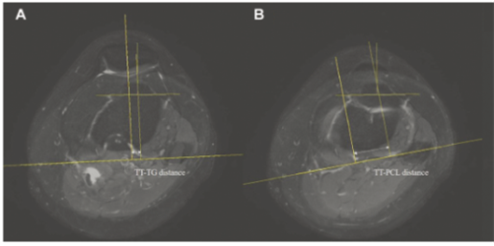

| ▲A. 경골결절과 활차구 사이(TT-TG) 거리- 슬개건이 닿는 부위의 중심을 지나는 직선과 활차구 홈의 가장 깊숙한 부분을 지나는 직선 사이의 거리 B. 경골결절과 후방십자인대 사이(TT-PCL) 거리- 슬개건이 닿는 부위의 중심을 지나는 직선과 후방십자인대의 안쪽 모서리를 지나는 직선 사이의 거리 |

물리 치료나 보조기 착용 등 보존적 치료에도 탈구가 반복되면 수술적 치료를 고려하게 된다. 성인의 경우 경골결절(정강이뼈에서 가장 튀어나온 부분)과 활차구 사이(TT-TG) 및 경골결절과 후방십자인대 사이(TT-PCL) 거리를 측정해 TT-TG 거리 20mm 또는 TT-PCL 거리 24mm을 기준으로, 이보다 큰 경우 심각한 불균형이 있다고 판단하고, 슬개골을 제자리에 되돌려놓는 ‘원위부 재정렬 수술’을 시행하게 된다.